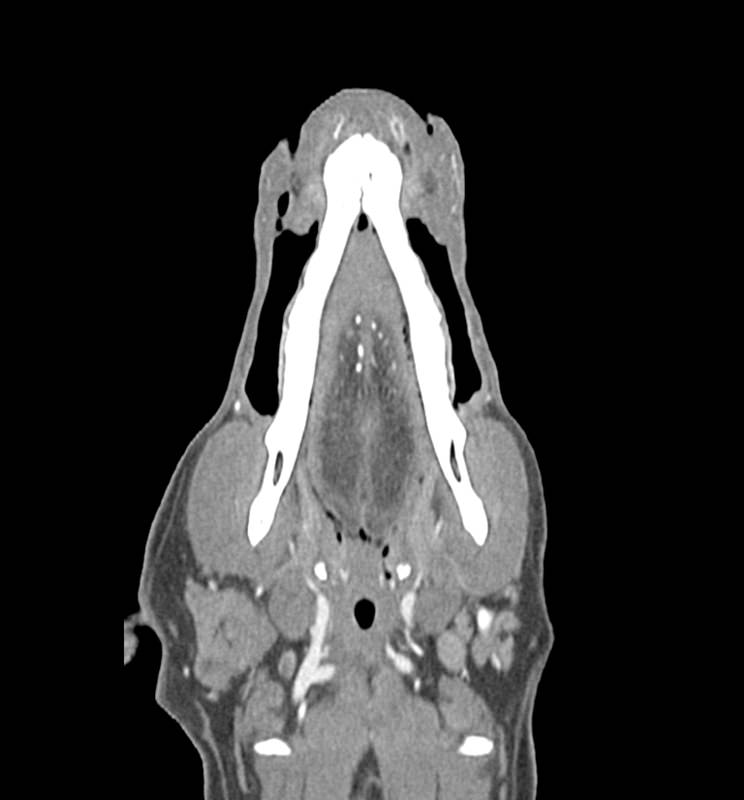

Fantom poskytuje realistickou CT simulaci psí hlavy bez kontrastní látky. Kosti a měkké tkáně jsou autenticky zobrazeny s realistickými hodnotami CT pro všechny tkáně při napětí trubice 120 kVp v CT skeneru. Vzduchové prostory jsou vyplněny kompozitem z celulózového polymeru s přibližně -80 Hounsfieldovými jednotkami. Pokud má být fantom používán primárně při jiném napětím trubice (např. 100 kVp), lze kalibraci hodnot CT v případě potřeby odpovídajícím způsobem upravit. Fantom také poskytuje realistické kontrasty tkání při rentgenovém zobrazování.